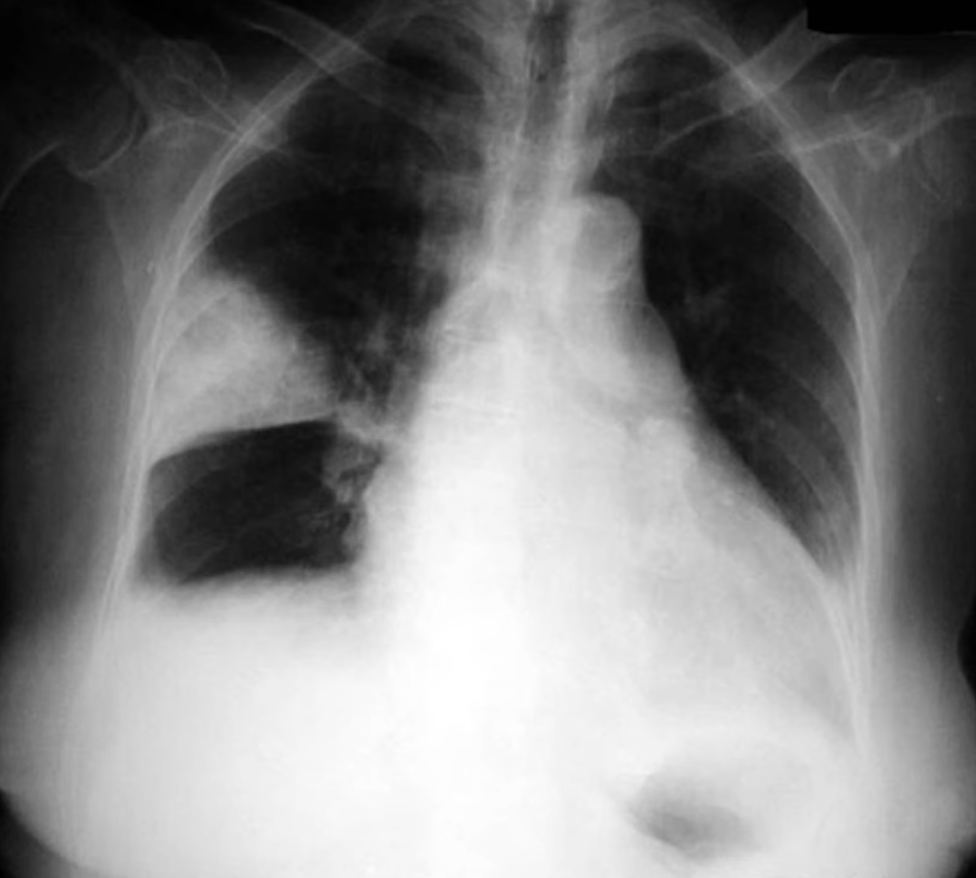

Pleural Effusion

Small effusions are often first visible on the lateral film before the AP.

Subpulmonic Effusion

Fluid accumulation between the lung base and the diaphragm, not tracking up the pleura and therefore not blunting the costophrenic angle.

Suggested by:

- Diaphragm appears to peak more laterally than normal

- Diaphragm appears more horizontal than normal

- On left: abnormally large distance between gastric bubble and lung base

- On right: abnormally high horizontal fissure